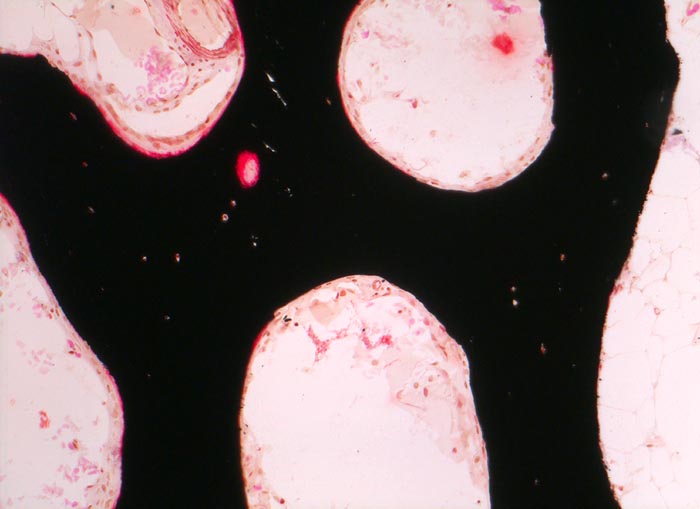

PathoPic ID 3508 - normales Osteoid

normales Osteoid

Knochenmark, Beckenkamm

Knochen, Knorpel, Gelenke

Schmaler roter Osteoidsaum.

Histologie

100